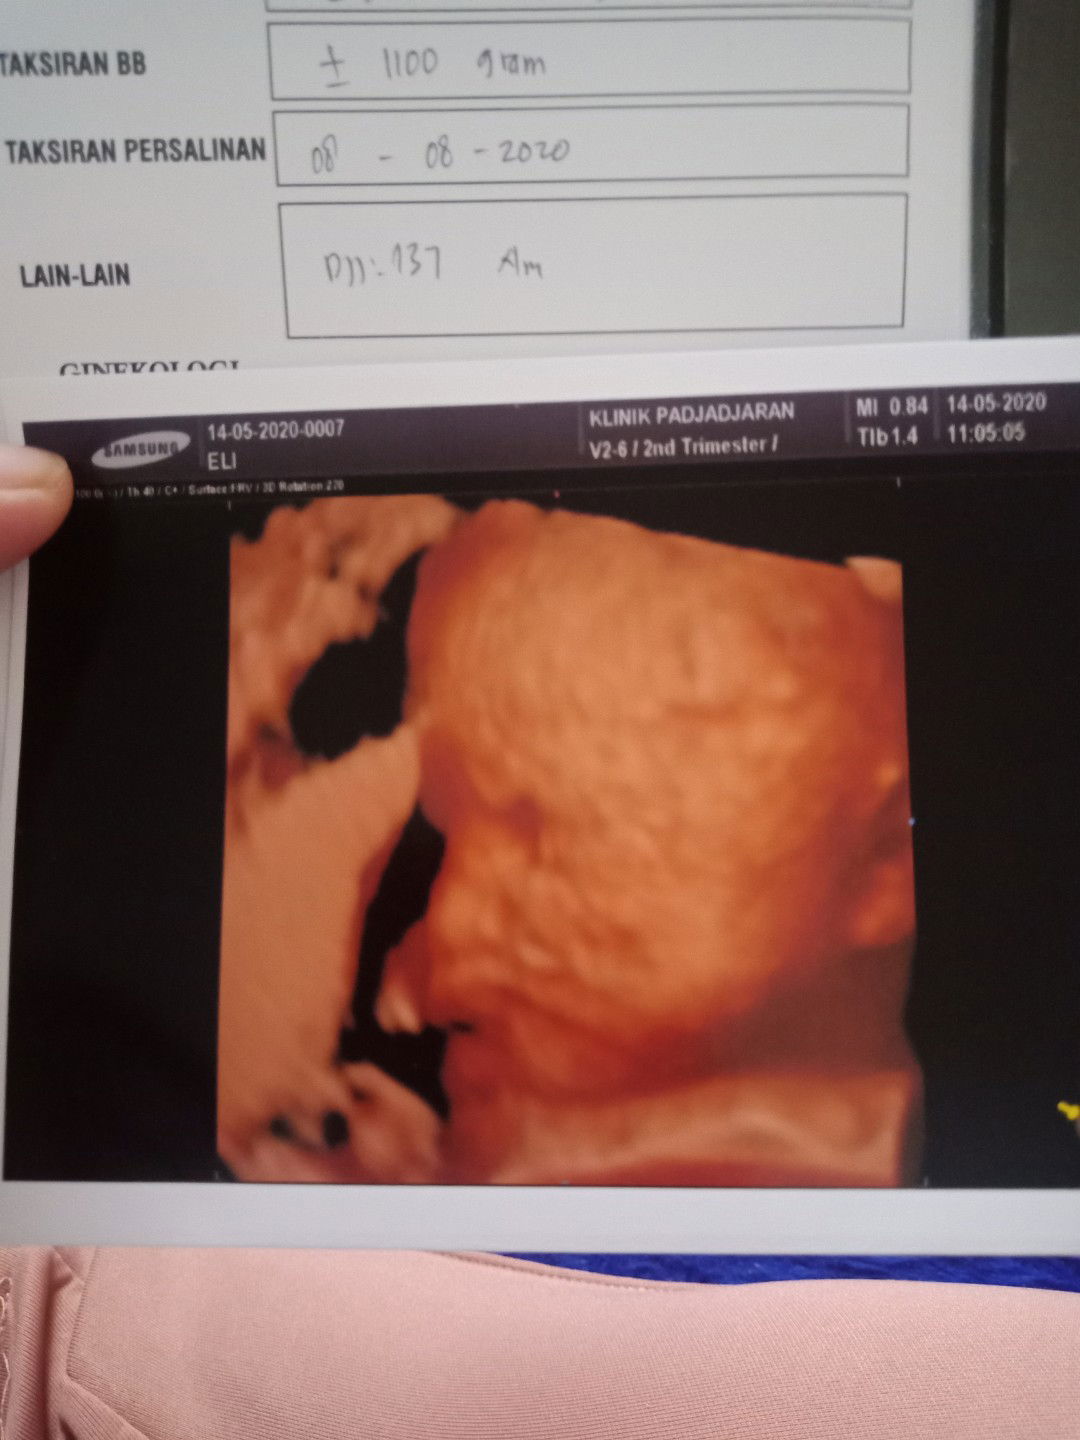

Hasil usg selama 4 bulan 6x USG

Sekedar cerita aja ya bun, Alhamdulillah bun aku seseneng itu lihat perkembangan kehamilan pertama ini , udah 6x USG penuh dengan cerita suka dan dukanya. tiap usg membuat aku senyum2 sendiri,terharu masyaallah ada dedeknya d dalem perutku ? 1.Usg pertama 11Desember2019,aku putusin usg karna udah telat haid slma seminggu dan bnyak perubahan dlm tubuhku dri mualmuntah,sakit payudara. pas usg baru penebalan dinding rahim ,belum terlihat kantung apalagi janinnya. Usg pertama ada kecewanya, sedih dokter belum bisa mastiin aku hamil dan di suruh 2 minggu lgi untuk usg ulang . kta dokternya klo liat dri hsil tespek 70% kemungkinan hamil. 2. Aku usg ulang tgl 07 Januari 2020, setelah menunggu 4 minggu belum haid juga dan mual muntahku smkin mningkat. aku putusin usg lagi mskipun sempet hawatir takut kecewa lgi sama hasilnya. Dan alhamdulillah udah keliatan kantung dan janinnya. 3. usg k 3xnya,20 januari 2020 aku HB sama suami (maap) pdahal baru di mulai bbrpa detik aku lap pke tisu ada cairan coklat gitu . dan kita ga lanjutin, aku berbaring bbrpa jam terus pas aku pipis liat cd ku ada flek coklat . aku baringin lagi aku merasa ga enak perut dan membuat aku semakin waswas aku panik sampe nangis ga karuan . Saat itu lg hujan aku putusin ke bidan terdekat , bidan bilang bismillah aja smoga gpp . aku kurang puas dengan jawaban bidan takut kenapa2 , pulang dri bidan ku liat cd ada flek darahnya aku semakin ga karuan . aku nangis terus2an bun saking paniknya . kemudian hari mulai malam nyari2 dokter spog yg msih buka , walaupun kita harus ngantri lama karna dadakan . sambil nunggu ,nangis terus2an aku sampe pusing tensi tinggi kmudian aku d bwa ruang igd sambil nunggu dokternya . Setelah nunggu alhamdulillah ternyata kata dokter janinnya gpp, baik2 aja . mungkin darah itu karna ada luka di dlm ,tapi bukan dri kandunganku . dokter nyuruh puasa dulu sama suami . 4.usg k 4x tgl 30 januari 2020 , setelah 10 hari aku bedrest fleknya blum hilang juga pdahal udh d ksih penguat kandungan sama dokter, udah bedrest ,dan puasa juga sama suami aku msih panik takut janinnya knpa2 . aku putusin ke spog lagi . beda dokter lagi tapi jawabannya msih sama dede nya baik2 aja , butuh full bedrest aja . dokter bilang flek memang gejala awal keguguran ,apalagi keluar darah selama hamil aplgi usia khamilan yg msih muda itu ga boleh . dokter bilang lihat 2minggu kedepan klo usia nya sudah diatas 13 minggu mulai kuat,jdi di sarankan untuk full bedrest,minum pnguat kandungan dri dokter,dan puasa hb sama suami. 5.usg k 5x nya tgl 13Februari2020, setelah 2 minggu usg ,alhamdulillah selama itu pula aku bedrest aku ga ngalamin lagi flek . Dokter bilang semuanya baik2 aja , dan usg k 5 ini ada yg beda biasanya usg 2D aja dan usg saat itu usg 2D + 3D/4D jd hasil poto usg nya 2 . hasil usg nya usia khmilan saat itu 13w2d . dokter nyuruh usg slnjutnya dijadwalin bulan depan ,sebulan lagi kalo memang gaada keluhan apapun. 6. 12 Maret 2020, nungguin sebulan berasa lama gasabar pengen liat perkembangan dede nya karna aku belum ngerasain kedutan apapun di perutku pdahal UK sudah 17week? . hasil usg nya alhamdulillah prkembangan dede nya semakin bagus , tapi UK setara dengan 18-19 minggu . seminggu lebih tua karna bbj nya 240gr ,tapi dilihat dri apk UK 17 mnggu itu harusnya 110-140gr . aku sempet khawatir juga tapi dokternya bilang normal2 aja . oh iya seperti bulan sblmnya usg k 6x juga 2D+3D/4D lagi , dan poto usg yg 2D nya kali ini hanya kepala sama perut . tapi dokternya udah jelasin semuanya sewaktu usg . nah gitu bun ceritaku selama 4 bulan ini, alhamdulillah dinikmatin setiap prosesnya bersyukur banget bisa smpe di titik ini . 7.poto ke 7 itu acara tasyakur 4 blanan kemaren , alhamdulillah semua berjalan lancar . aku berharap kita semua, bunda2 dan dedeknya sehat2 hingga lahiran tiba ??.terimakasih untuk yg bersedia baca cerita kehamilanku ini ❤️?